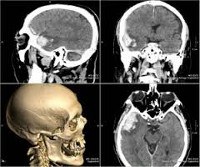

CT of the head.

Компьютерная томография головы. Методика диагностики для получения послойного изображения головного мозга, головного мозга и лица, черепа и мягких тканей головы. Это результат цифровой обработки данных, полученных при ослаблении рентгеновских лучей различными органами и тканями. КТ головы является одним из наиболее широко используемых методов диагностики для выявления поражений, врожденных пороков развития и приобретенных заболеваний различной этиологии. Высокое содержание информации, умеренное воздействие радиации и доступная цена КТ головы в Москве делают этот метод незаменимым в процессе диагностики широкого спектра патологических состояний головного мозга, костей и мягких структур головного мозга.

Выполняя сканирование головы, врач может исследовать трехмерное изображение, оценивая относительное положение, размер и форму нормальных структур и патологических структур. Еще одна особенность этой техники - высокое разрешение. С головкой сT точность оценки коэффициента ослабления составляет 0,5%. В стандартной рентгенографии этот показатель колеблется от 10 до 20%. Специальные компьютерные программы еще больше расширяют возможности КТ головы, позволяя создавать трехмерные модели внутричерепных нервов, сосудистых сетей и других структур.